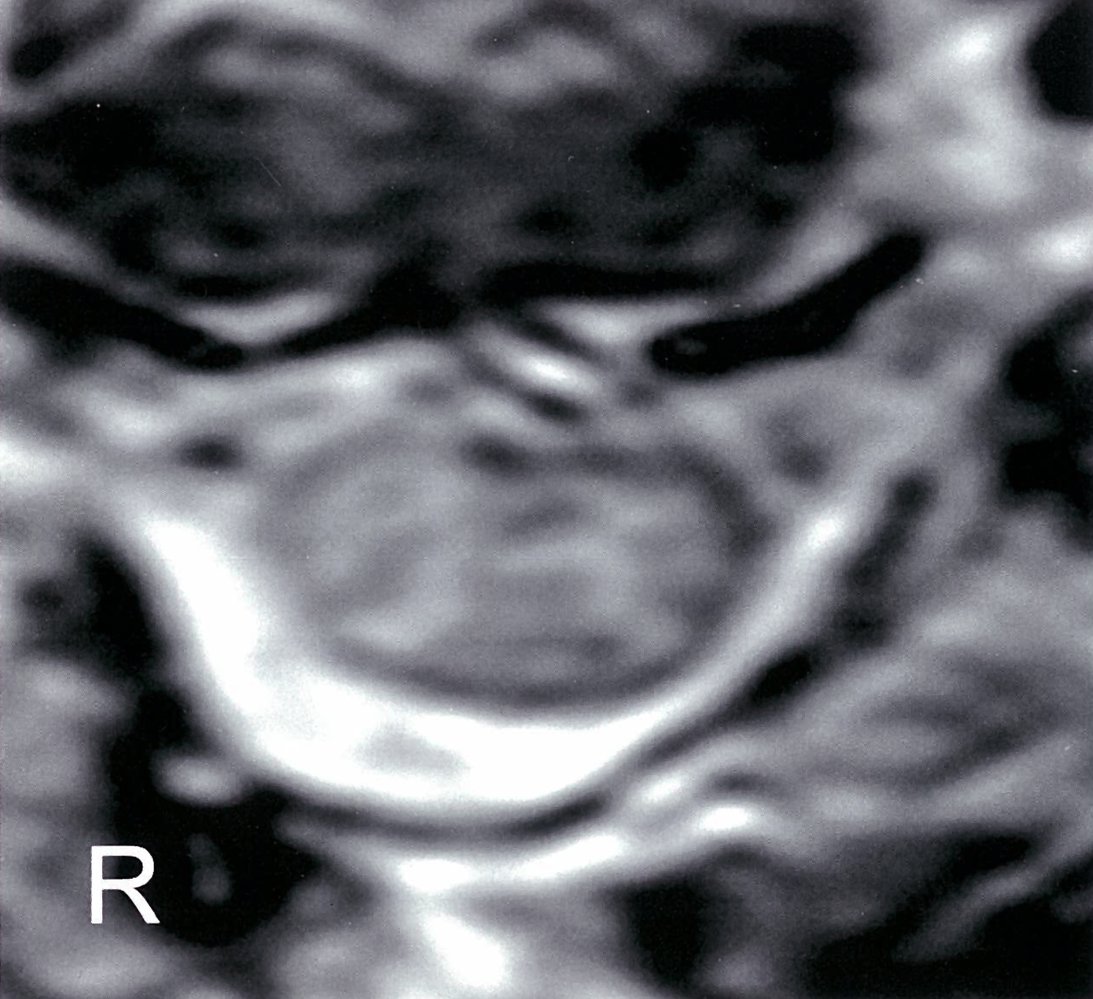

• MRI of the spine (imaging modality of choice) : determines the site of narrowing of the medulla and the underlying pathology

• Myelography (possibly with CT): if MRI is contraindicated (e.g., in patients with metal implants)